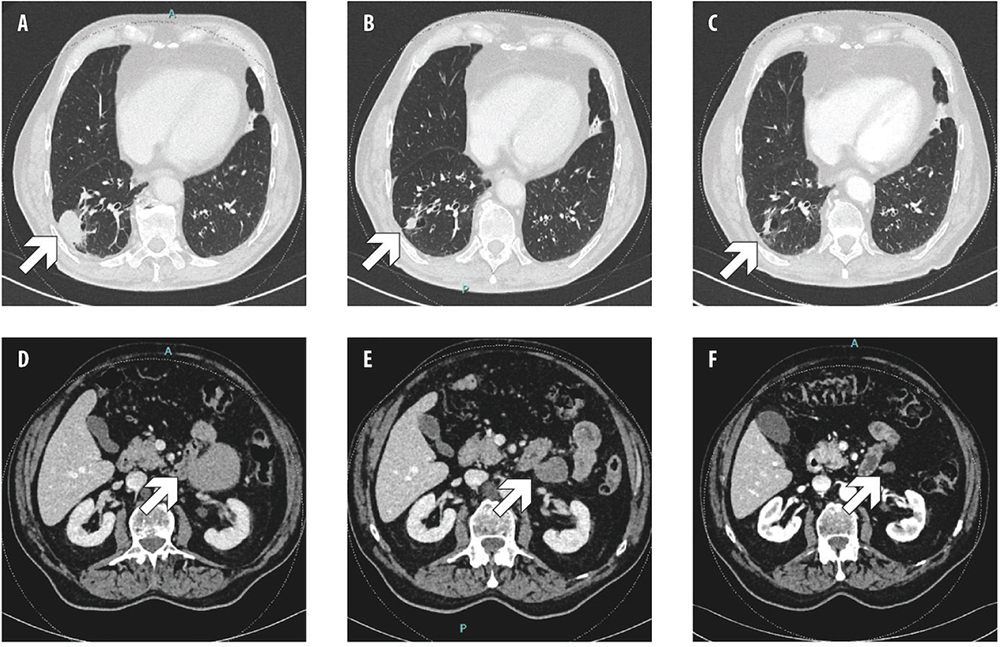

First-line tepotinib 500 mg/day was started through an Early Access Program. The patient achieved partial response at the first tumor assessment after 3 months of treatment. Further response was observed at months 6, 9 and 12, then stable disease was observed (Fig. 2). During the treatment, the patient was diagnosed also with a prostate carcinoma (stage cT2 cN0, Gleason Score 4+4), therefore androgen deprivation therapy was added, without safety concerns. After 6 months of treatment with tepotinib, the patient developed treatment-related G2 peripheral edema; therefore, tepotinib was temporarily discontinued, and diuretics were administered, with complete regression of edema. Tepotinib was then restarted at 250 mg/day. After 16 months of treatment, however, tepotinib was discontinued again due to recurrent G2 peripheral edema. The patient received a further course of diuretics combined with physical therapy (i.e., compression stockings, retrograde massage), achieving edema improvement at G1; then, tepotinib was restarted at 250 mg/day. After 23 months of treatment, tepotinib was reduced at 250 mg every other day because of worsening edema, and it is currently ongoing (after 31 months).

Fig. 2 - Computed tomography (CT) scan showing, respecively, primary lung tumor and peritoneal metastasis at baseline (A, D), after 12 weeks (B, E) and 1 year (C, F) of tepotinib.